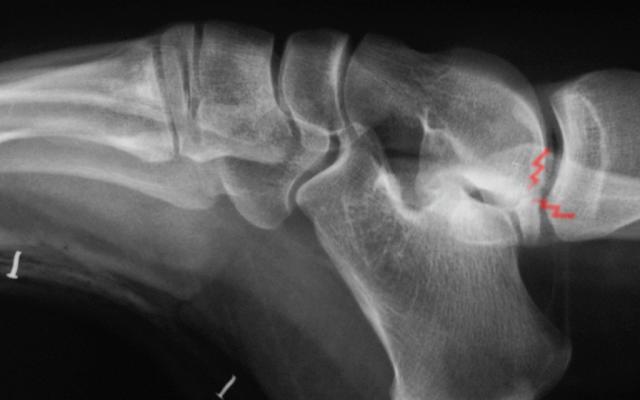

Anterior and posterior impingement with lateral ossicle

37 Years old male with low physical activity and BMI of 32.